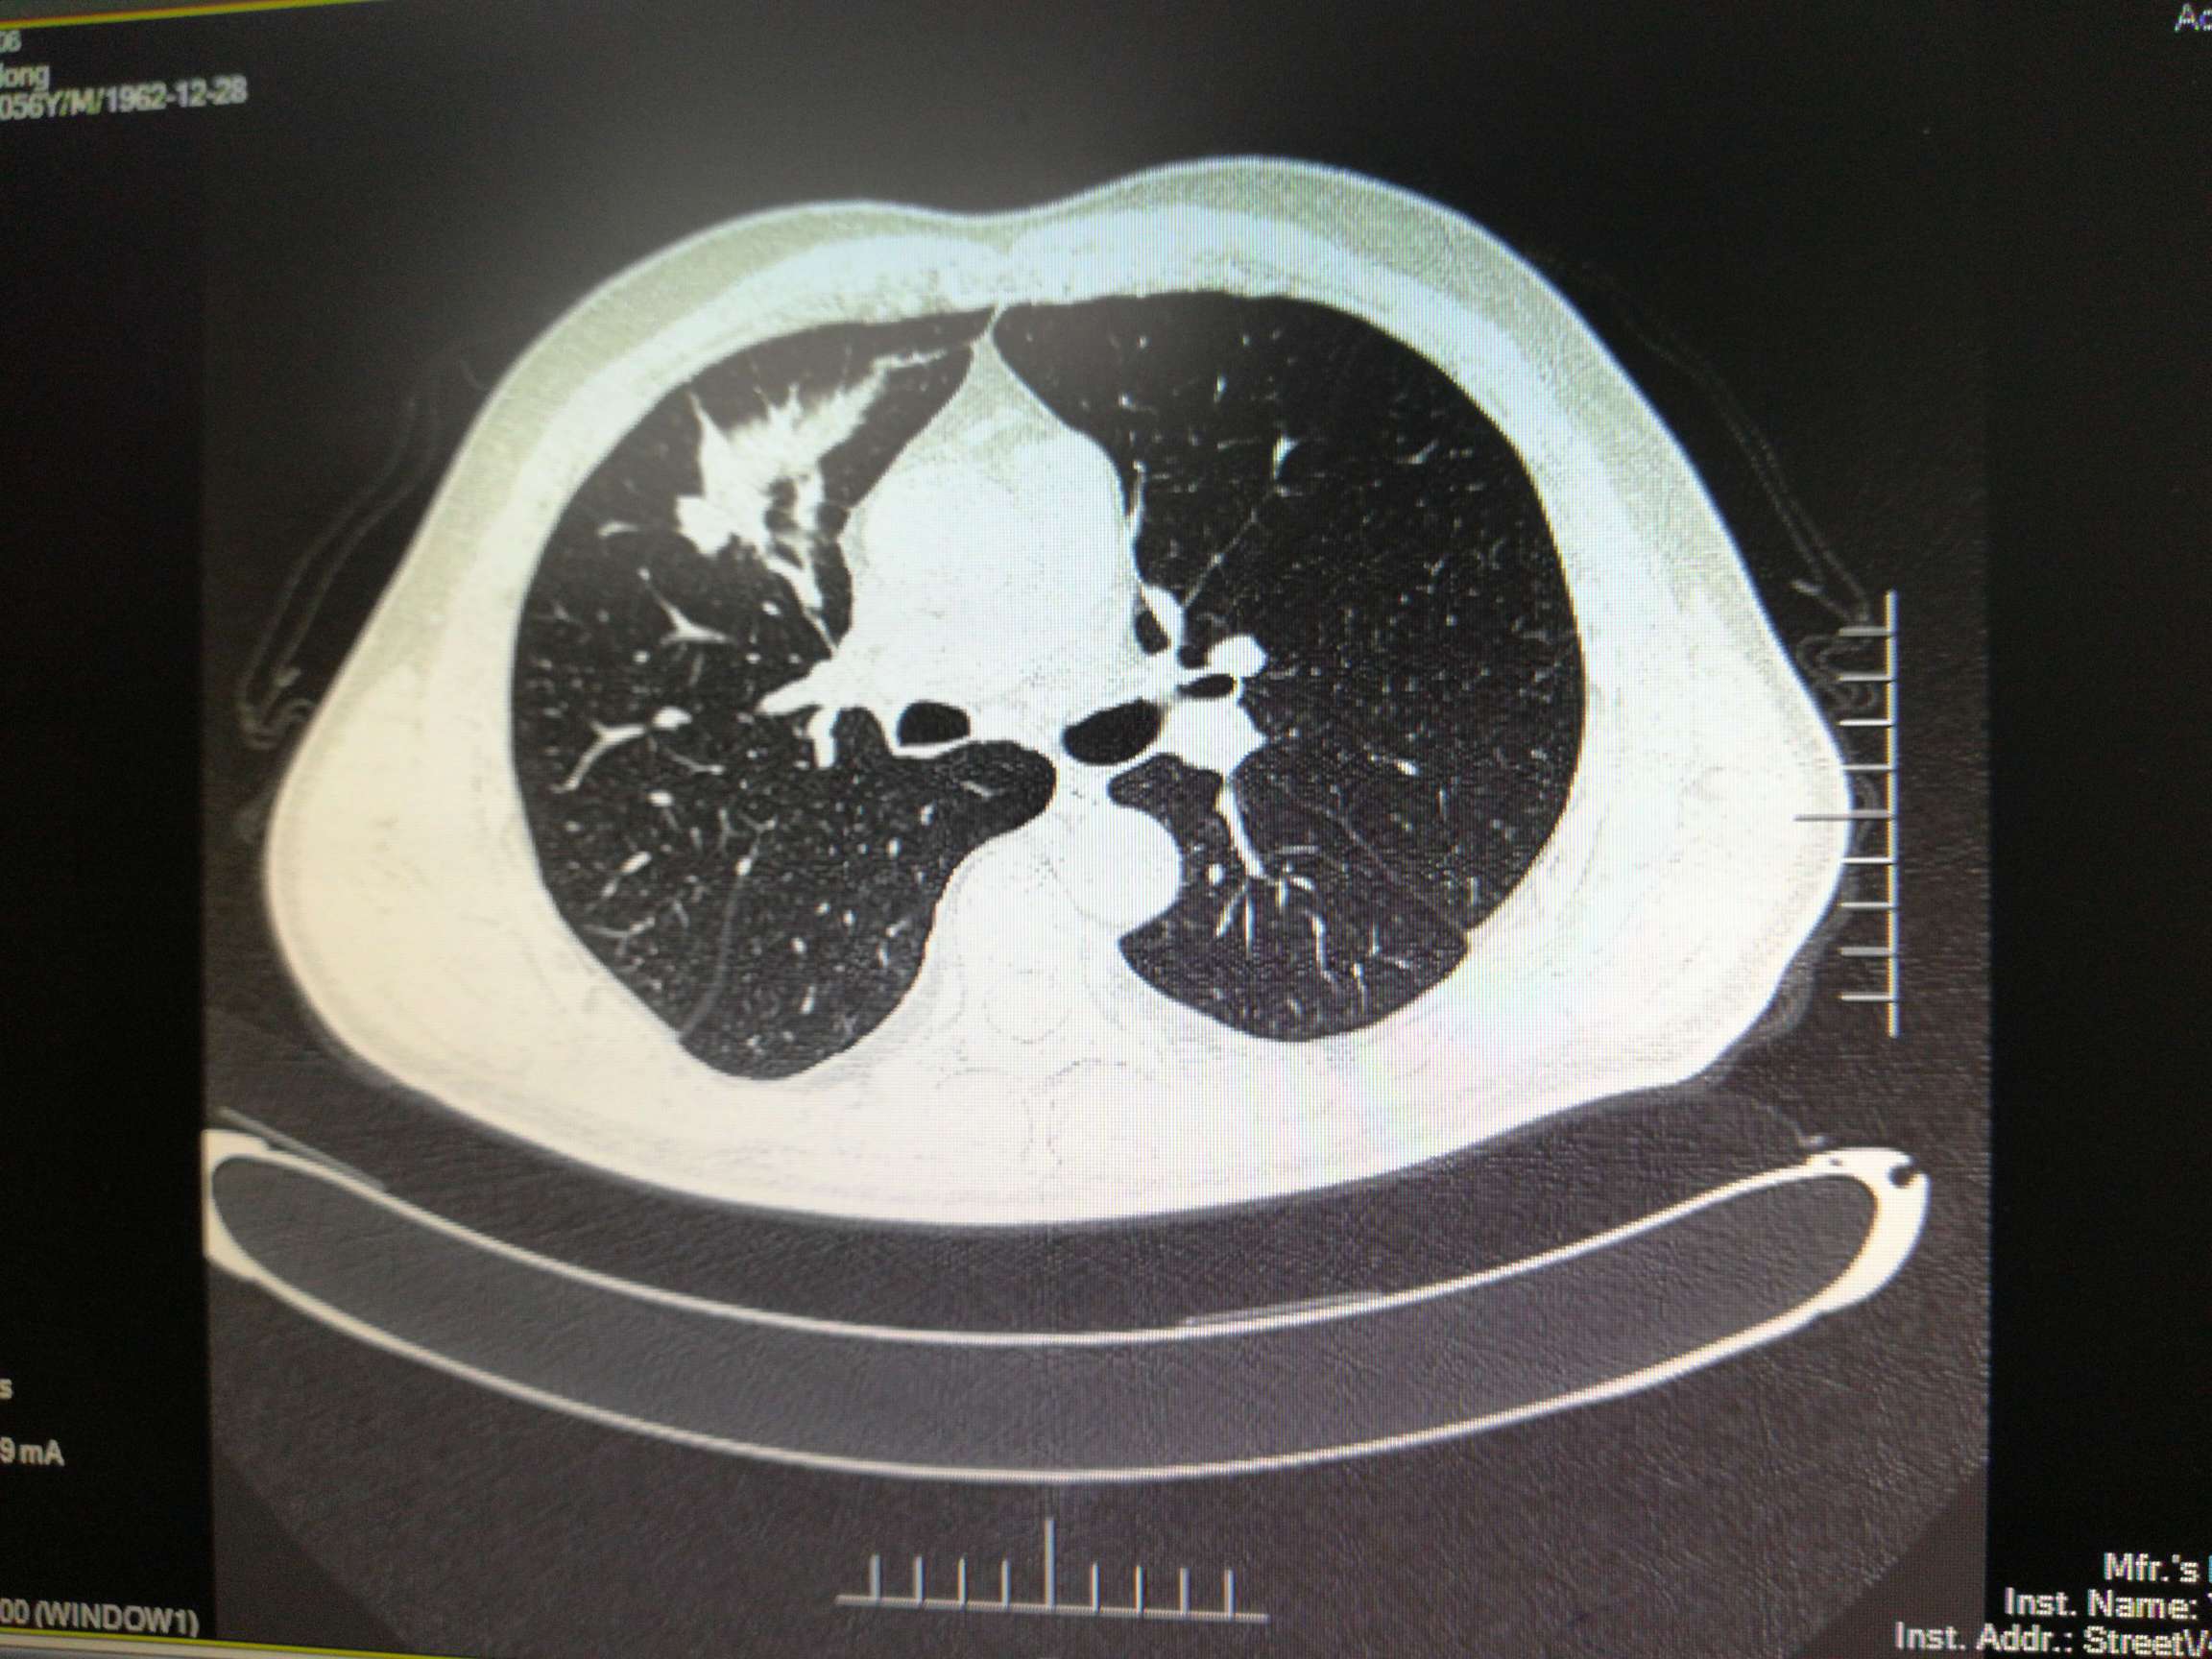

胸部右肺叶前段有3.4*6.7cm原发灶,右侧叶间裂、胸膜多处转移,纵膈内、右肺门旁、心隔角多处淋巴结转移,较大者1.3*1.0cm。有少量胸水。

期间病情迅速控制,原发灶从6. 7*3.4cm减小为1.7*1.5cm,头部从2.4*1.8cm减小到1.1*0.9cm,淋巴结较大者一直为1.3*1.0cm。胸水抽了两次,打了恩度,之后胸水没有再犯。肿瘤指标物一直减小。骨髓抑制严重。

10月份复查,cea继续缓慢上升,糖类125也开始上升。Ct显示原发灶从1.4*1.2cm增大到为2.7*1.4cm。pet-ct显示没有远端转移,头部转移灶失去活性,胸部原发SUVmax4.2,淋巴结SUVmax3.2。骨髓抑制现象继续持续,白细胞3.8,淋巴细胞百分比46.3%,中性细胞36.10%。在用K药之后再测白细胞3.2,可能骨髓抑制与K药有关。病人体感很好。总体判断为耐药迹象。